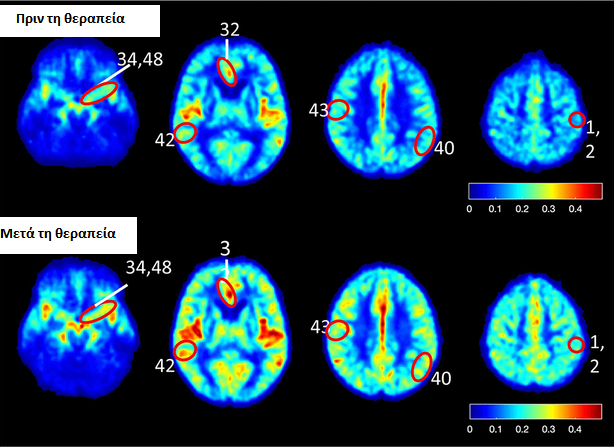

Σύμφωνα με όσα αναφέρονται στην επιστημονική επιθεώρηση Aging, έπειτα από 60 συνεδρίες με υπερβαρικό οξυγόνο στη διάρκεια 90 ημερών, η ροή του αίματος στον εγκέφαλο των έξι ατόμων βελτιώθηκε κατά μέσο όρο 20%. Επίσης, τα τεστ μνήμης, στα οποία υποβλήθηκαν στη συνέχεια, έδειξαν μέση βελτίωση των γνωσιακών ικανοτήτων τους κατά 16,5%.

Η επιστημονική ομάδα εκτιμά ότι η θεραπεία λειτουργεί αλλάζοντας τη δομή των αγγείων του εγκεφάλου και τα διευρύνει ώστε να μπορεί να περάσει περισσότερο αίμα.